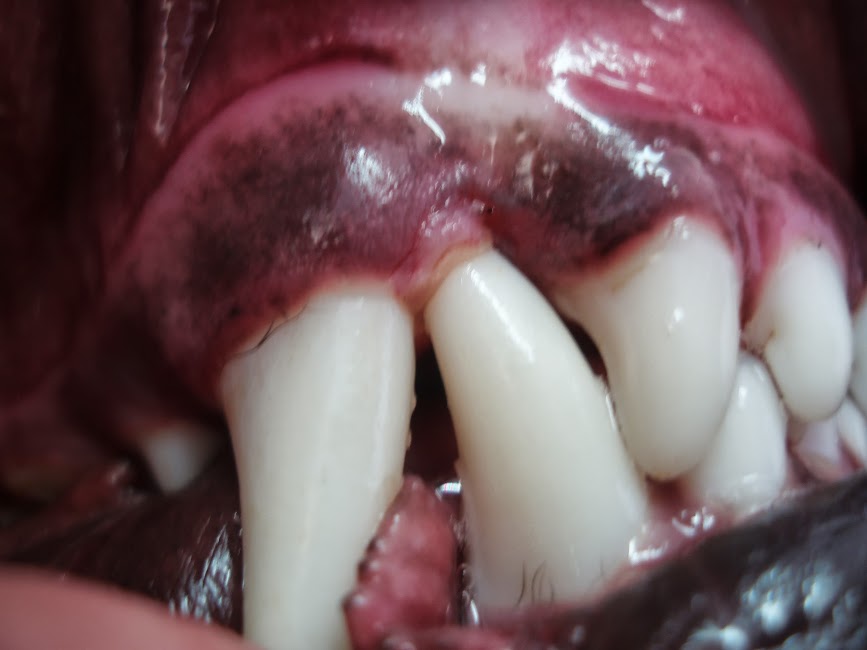

Close Up of Dog Dirty Teeth, Dental and Gum Disease in Dog, Unhealthy Dog Mouth Turning Red One of the signs of high blood. A bright red tongue could indicate a variety of doggy health conditions, such as dehydration or overheating, stomatitis (oral inflammation), high blood pressure. These conditions usually come with other symptoms, such as high body temperature and coughing. when a dog’s tongue takes on another color, like bright red, this can be indicative. Dog Mouth Turning Red.

From bellambivet.blogspot.com